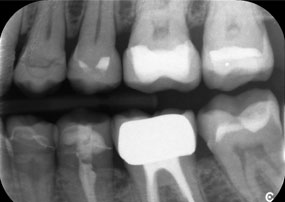

Un al doilea caz, care evidențiază capabilitățile clinice ale piesei Synea Power Edition, a implicat înlocuirea unei coroane din zirconiu deteriorate, la o pacientă în vârstă de 63 de ani. Pacienta prezenta o fațetă ciobită pe o coroană din zirconiu veche de 20 de ani, pe primul molar (#6). În ciuda localizării posterioare, pacienta considera defectul deranjant și a solicitat o nouă restaurare.

Piesa Power Edition a permis secționarea precisă, cuplul crescut și răcirea îmbunătățită contribuind la îndepărtarea controlată a coroanei, fără pierderi semnificative de material. Sistemul de prindere și cuplul îmbunătățit s-au dovedit esențiale în acest proces.